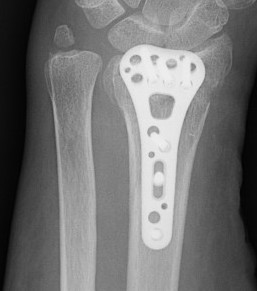

Undisplaced wrist fracture

- interrupts blood supply at a watershed area

- between 3 weeks and 3 months post injry